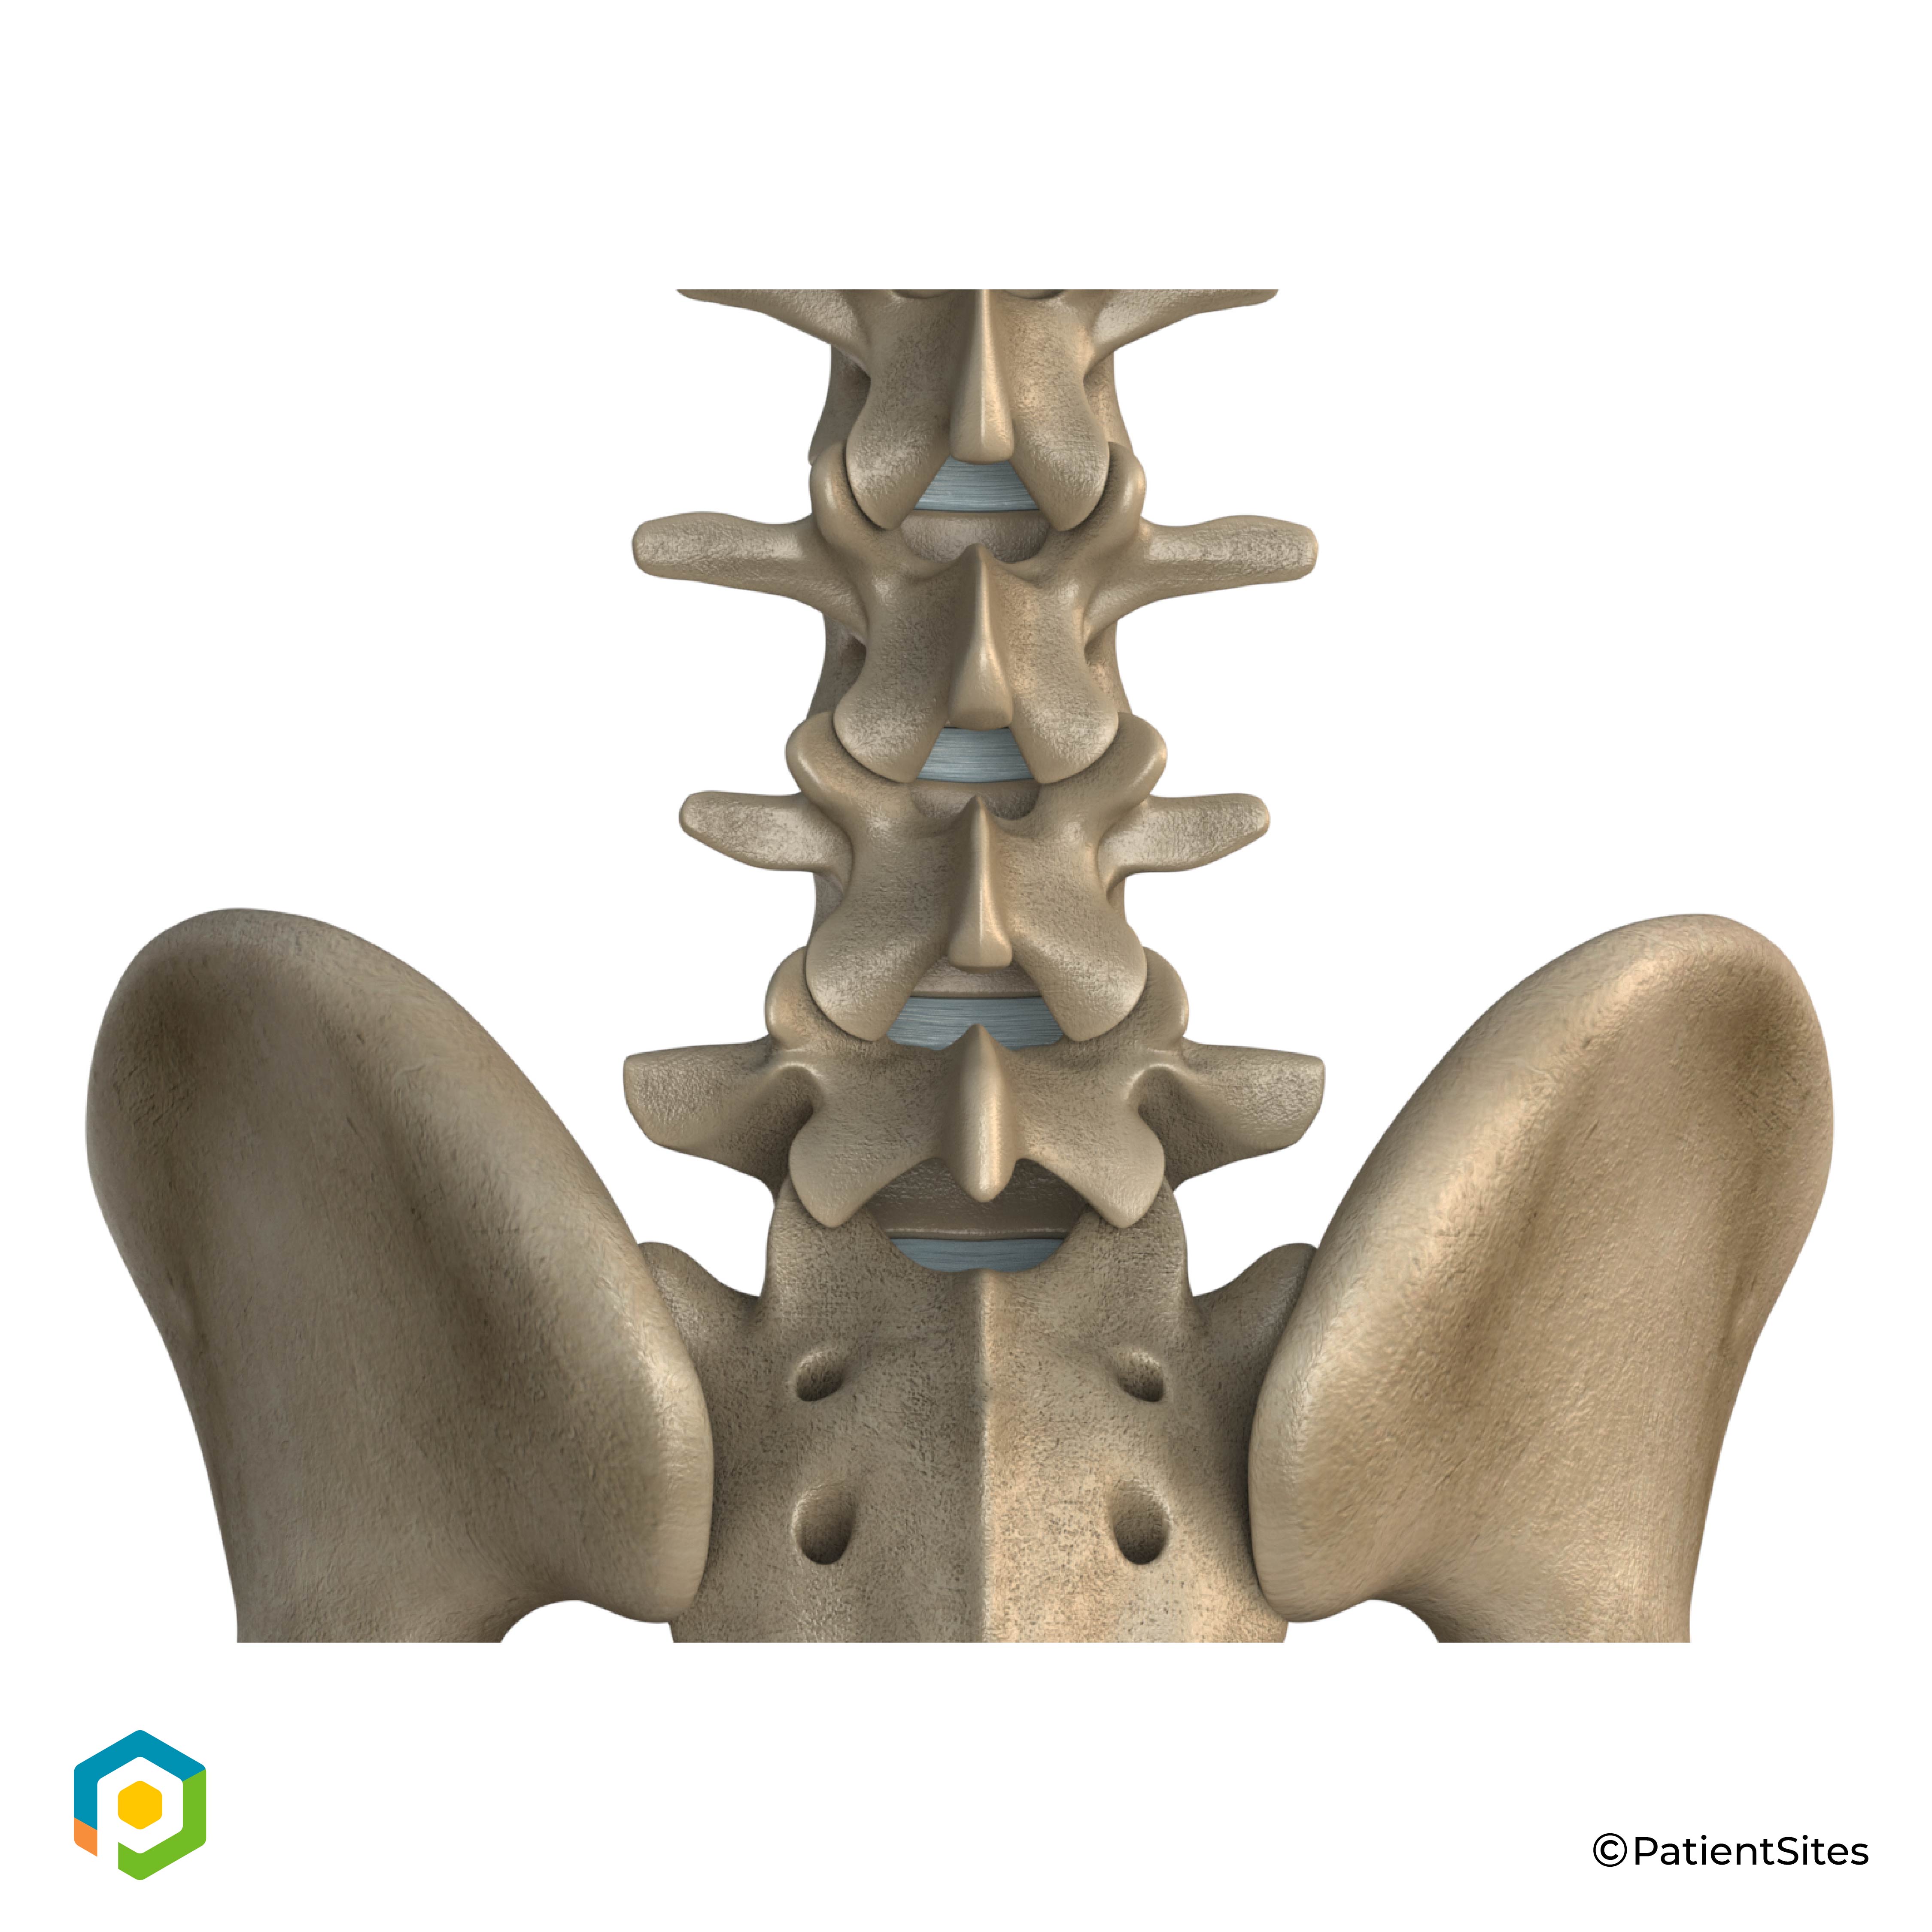

Anatomy

What part of the back is involved?

The human spine is made up of 24 spinal bones, called vertebrae. Vertebrae are stacked on top of one another to create the spinal column. The spinal column gives the body its form. It is the body's main upright support.

Human Spine

The back portion of the spinal column forms a bony ring. When the vertebrae are stacked on top of each other, these bony rings create a hollow tube. This tube, called the spinal canal, surrounds the spinal cord as it passes through the spine. Just as the skull protects the brain, the bones of the spinal column protect the spinal cord.

Between the vertebrae of each spinal segment are two facet joints. The facet joints are located on the back of the spinal column. There are two facet joints between each pair of vertebrae, one on each side of the spine. A facet joint is made of small, bony knobs that line up along the back of the spine. Where these knobs meet, they form a joint that connects the two vertebrae. The alignment of the facet joints of the lumbar spine allows freedom of movement as you bend forward and back.